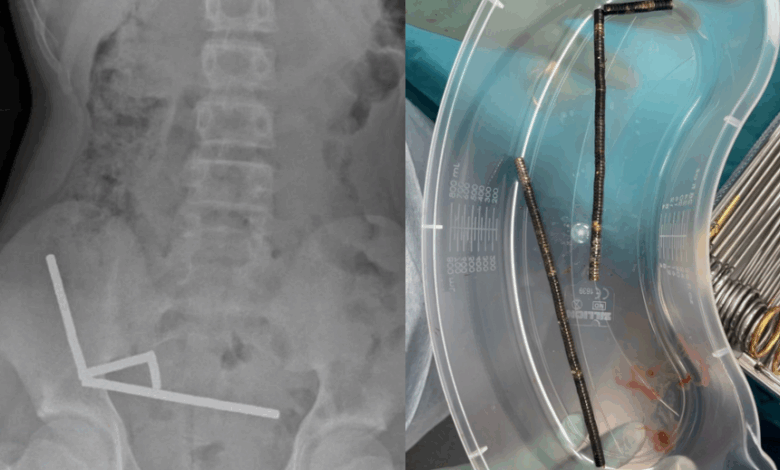

Upon arrival at the hospital, the boy disclosed that he had swallowed the magnets approximately a week prior. Scans revealed that the magnets had formed four chains within his bowel and at the beginning of his large intestine. Due to the disruptive nature of the magnets in his body, doctors opted for exploratory surgery to address the issue.

During the operation, surgeons discovered that the magnet chains had caused pressure necrosis in the bowel and large intestine. This condition occurs when tissue dies due to prolonged pressure. Fortunately, the surgeons were able to successfully remove the magnets, and the boy recovered after an eight-day hospital stay.